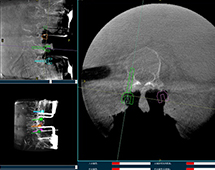

機(jī)器人輔助腰椎后路側(cè)彎矯形手術(shù)方案解析

機(jī)器人輔助腰椎后路側(cè)彎矯形手術(shù)是什么原理?下面帶來一例機(jī)器人輔助腰椎后路側(cè)彎矯形手術(shù)方案,該手術(shù)在南京醫(yī)科大學(xué)第二附屬醫(yī)院進(jìn)行,所用設(shè)備為普愛脊柱外科手術(shù)機(jī)器人PL300B+三維C形臂PLX7500A。...